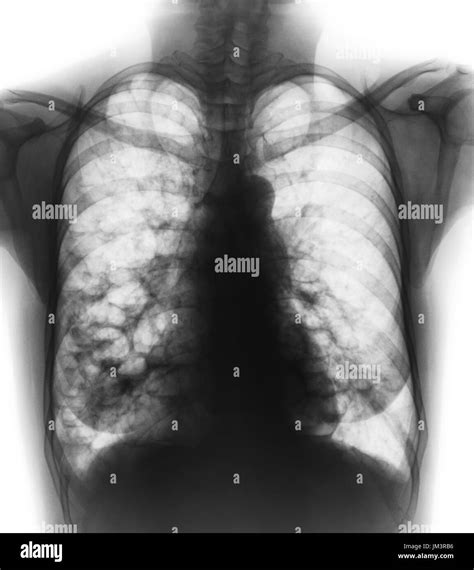

Because blebs in lungs are usually invisible on a standard physical examination, doctors rely heavily on imaging technology to detect them and assess the extent of a pneumothorax if it occurs.

Chest X-Ray The first-line approach to identify a collapsed lung or locate air pockets.